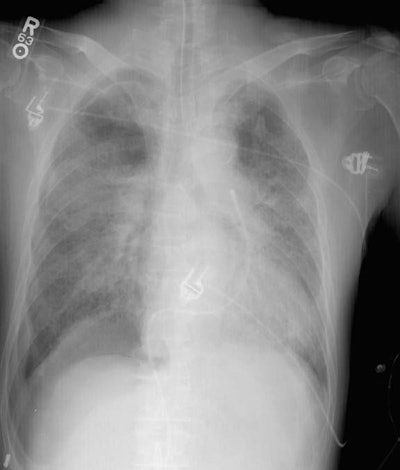

On the initial film, the right costophrenic sulcus was cut off the film, but was suspicious for a "deep sulcus sign"- an indication of a pneumothorax in a supine patient. A repeat examination (below initial image) was performed which nicely demonstrated the "deep sulcus" on the right, as well as a pleural line in the right upper lung indicating that the pneumothorax had enlarged in the interval between the two films. This case demonstrates the need to include the costophrenic angles on all portable films.

Repeat exam:

The repeat exam demonstrates the "deep sulcus" on the right, as well as a pleural line in the right upper lung indicating that the pneumothorax had enlarged in the interval from when the initial film was performed.